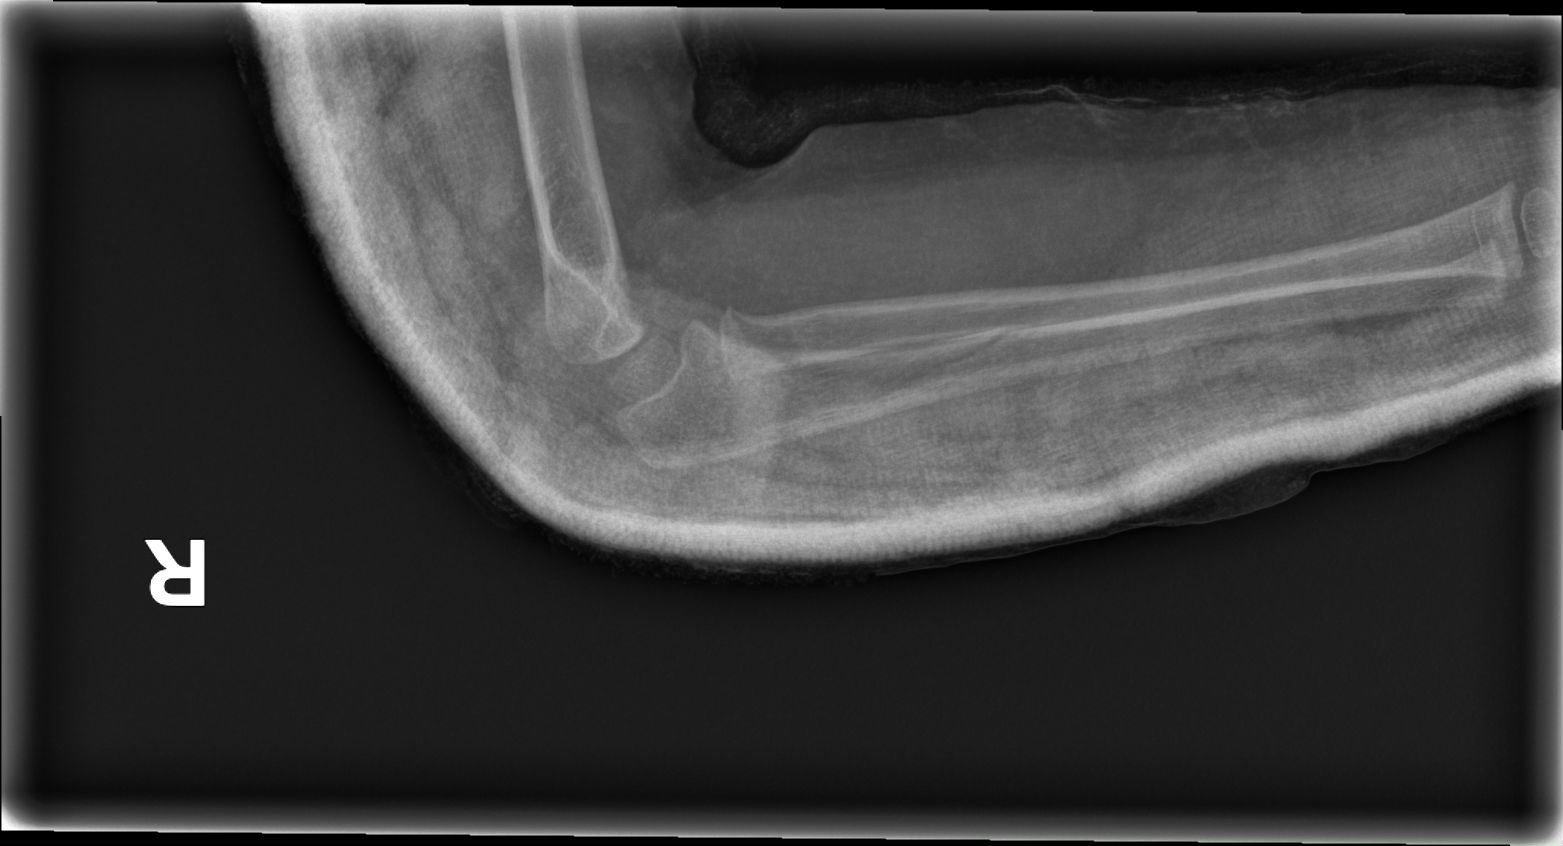

Fig. 1. Radiografía lateral del codo derecho que permite establecer el diagnóstico.

Niña de 3 años que acude al Servicio de Urgencias Pediátricas por dolor en el antebrazo derecho tras una caída. La madre refiere que no ha habido mecanismo de tracción. Tras la administración de analgesia, la paciente continúa con impotencia funcional y supinación mantenida. Se realiza radiografía de codo derecho, donde se observa la siguiente imagen (Figura 1).